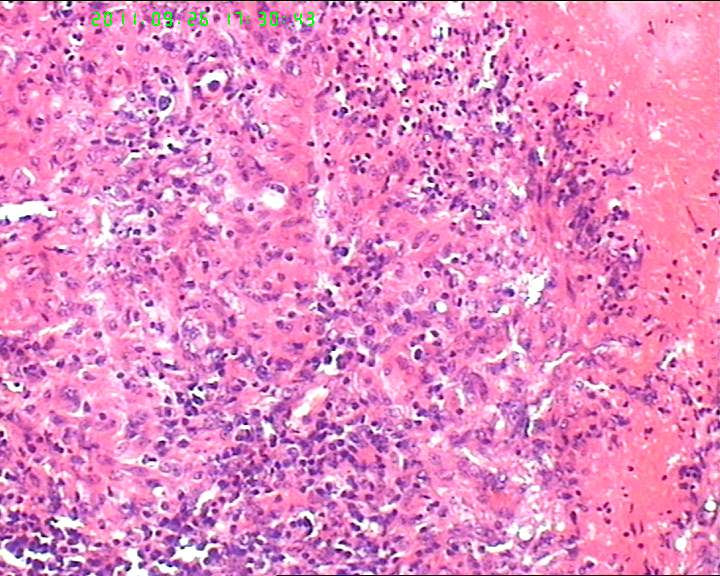

灰白不整形肿物一个,大小3.5*2.5*2cm,包膜完整。

21岁女性左侧颌下淋巴结,该诊断什么?图2

慢性肉芽肿性炎症,形态学倾向结节病,但是作为病理工作者对于这样的病例,再结合咋们国情,还是建议临床除外增殖性结核后再考虑结节病。

肉芽肿性炎症,倾向结节病。

最好做做抗酸染色、网状纤维染色和PAS后看看再定。